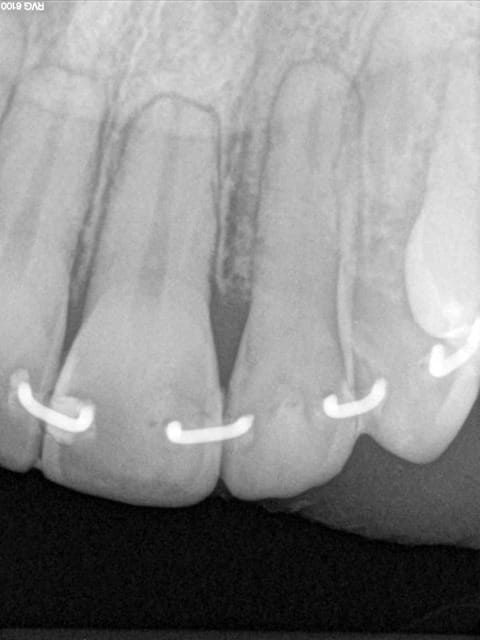

Les attelles d'Abjean j'en pose chaque semaine (ou presque), l'avantage ENOOOOORME par rapport à un "jonc noyé" c'est la rétention 3D que tu n'as pas avec le jonc!

et le délabrement est bcp moindre, en plus quand une attelle lache tu la changes, et pas tout le bastringue!

les miennes tiennent plus de 10 ans...

J'aime beaucoup mon "bridge provisoire" suite à la luxation de la 31 avec fracture de l'apex...^^ elle a tenu 8 ans.

En attendant, ce type de contention transitoire pendant une phase de guérison parodontale après TT ortho (suite aux migrations dentaires) est idéale à mon avis.

3) tu fais une gorge horizontale reliant les 2 points de contact jusqu'à la dentine (prof 1 mm) fraise HL 008

4) un léger avant trou à la fraise boule 008 aux extrémités de la gorge (komet H 009)

5) forage basse vitesse prof 1 à 2 mm les puits doivent être le plus parallèle possible (dans le tiers proximal de la dent à distance raisonnable de la pulpe ;-)

6) confection de l'attelle grâce à une pince à bec plat fine modifiée qui te permet de faire toutes les tailles d'entre-axe

7) essayage et puis souvent réessayage et scellement ou collage si tu en as.

C'est comme cela que Le Pr José Abjean nous l'a appris...à la fac.

C'est joli, mais je trouve que sur les radio, les trous sont plus prodonds que la contention et je trouve cela invasif vs fil ou contention classique. Pour quelques cas bien précis, ok, mais pas trop fréquente l'indication non ?